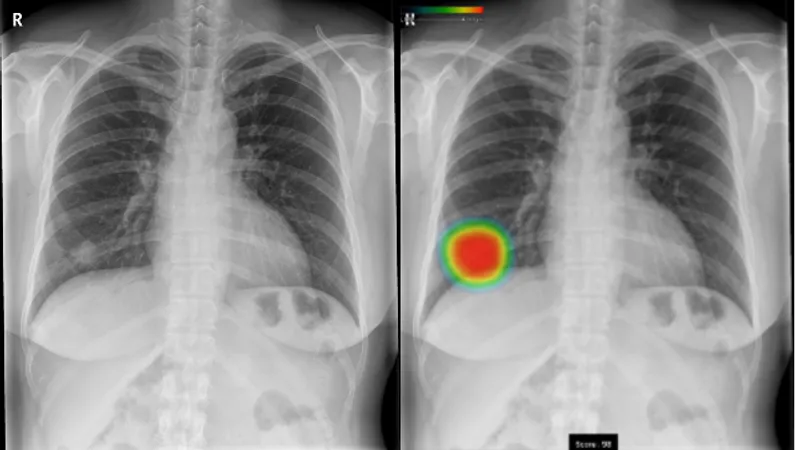

(1)ヒートマップ表示、スコア表示機能 結節・腫瘤影、浸潤影、気胸の候補領域を検出し、それらの異常領域の存在の可能性(確信度)を青から赤までのグラデーションカラーで表示します。確信度が低いほど青く、高いほど赤く表示します。また、各検出領域に対応する確信度の最大値をスコアで表示します。 (2)3つの画像所見に対応 本ソフトウェアの検出対象は、主要な肺疾患の画像所見である結節・腫瘤影、浸潤影、気胸の3所見です。健康診断や日常診療などにおけるさまざまな胸部疾患の診療に幅広く活用いただけます。